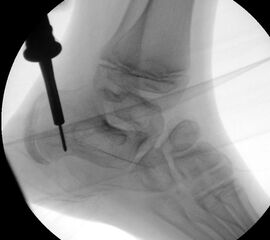

=> Risikoabwägung der radiologisch leicht erhöhten Strahlenbelastung intraoperativ

In der minimalinvasiven Fußchirurgie ist es unabdingbar, die Fräse in ihrer Position zum Knochen radiologisch zu kontrollieren, damit vulnerable Wachstumsfugen oder angrenzende Gelenke nicht verletzt werden. Zu diesem Zweck werden mit einem Bildwandler während der Operation die genaue Position der Fräse und der Osteotomieverlauf überprüft, was die Strahlenbelastung im Vergleich zu offenen Verfahren erhöht. Diese Strahlenbelastung hat potenziell einen schädigenden Einfluss auf den noch blutbildenden Knochen von Heranwachsenden. Gesicherte Landmarken am Fuß können die notwendige Zahl der Röntgenbilder und damit die Strahlung minimieren. Ist es erforderlich, mehrere Knochen zu osteotomieren, wie zum Beispiel im Bereich der Kleinzehen, werden anhand der Landmarken kleine Injektionsnadeln auf Höhe der geplanten Osteotomien vorgelegt und radiologisch im Bildwandler (BV) dokumentiert (Abb. 11). Ein solches Bild schafft eine gute Orientierung, sodass auf radiologische Kontrollen intraoperativ weitestgehend verzichtet werden kann.

Abb. 11: Lokalisation mehrerer Stichinzisionen mit einem Röntgenbild.